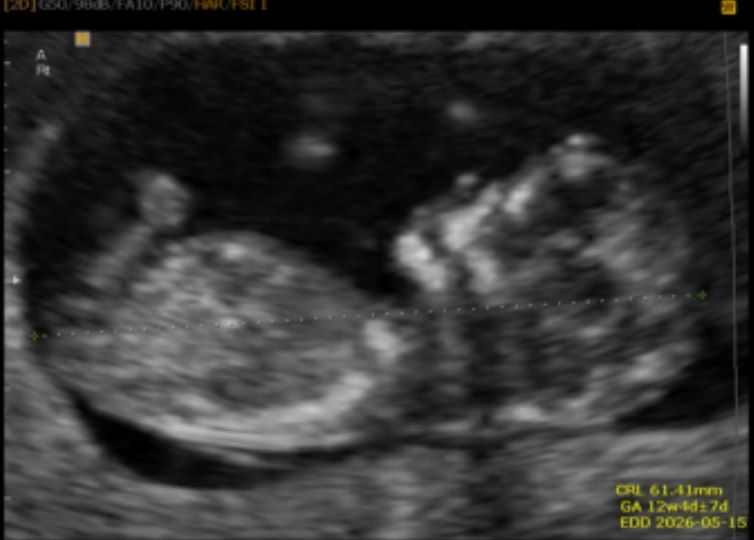

ارام67 مدیر استارتر عضویت: 1396/10/23 تعداد پست: 13590 سلام گلم غربالگری هم انجام دادی نمیدونم منظورت چیه سونو ان تی +ازمایش دادم از این کاربری دو نفر استفاده میکنن من و مامانم پس اگه تناقضی تو تاپیک ها دیدید تعجب نکنید